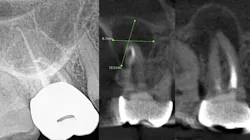

The periapical abscess that originates in the dental pulp is most often a secondary effect of dental caries. A periodontal abscess is an infection located contiguous to the periodontal pocket and may result in destruction of the periodontal ligament and alveolar bone. A periodontal abscess, the third most frequent dental emergency, has two ideologies: periodontitis related and nonperiodontitis related. Abscesses of periodontitis usually appear as an exacerbation of untreated periodontal disease or perhaps during periodontal treatment. Abscesses of nonperiodontitis-related origin frequently develop after the impaction of foreign objects, such as a piece of dental floss or abnormalities in the root enamel. A pericoronal abscess is associated with the crown of a partially erupted tooth. Like a gingival abscess, there may have been a retention of microbial plaque, food impaction, or trauma. The endo-periodontal lesions involve both the pulp and periodontal tissues, are relatively rare in clinical practice, and are one of the most challenging problems clinicians face (figure 1).

While I am not an expert, I do know that a bacterial infection inside or outside the mouth isn’t stellar for the entire body. In more than 30 years of clinical care, I can’t count the number of times I’ve seen a radiolucent area on a radiograph, when asymptomatic the treatment was nothing. There were other cases where the patient was in pain, given an antibiotic, and sent on their way. They didn’t have a follow-up appointment to treat the infection, perhaps because they couldn’t afford it or didn’t want treatment. I’m assigning no blame here, but simply stressing that we need to continue to educate our patients. Pathogens circulate and sometimes require the body’s immune system to be on overdrive, and many people’s health can’t afford to have an overactive immune system. Technology is expanding and dentistry can now utilize cone beam imaging to find abscesses that don’t present on a 2D radiograph. We can help our patients become healthier. But a silent abscess is an abscess. My friends in a Nashville dental practice recently had a case where the periapical radiograph looked completely fine, yet when a cone beam was done, an abscess showed up louder than Loretta Lynn at the Grand Ole Opry. We should be stewards of new knowledge, new technology, and be open to the expanding world of science.